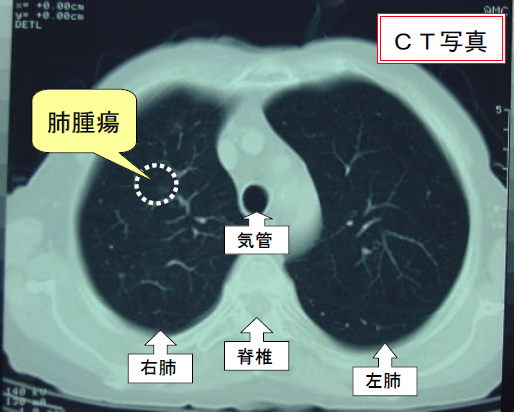

胸部CTを用いた肺ガン検診について | 市立秋田総合病院,胸部CTのおすすめ|日本赤十字社 熊本健康管理センター,レジデントノート増刊:読影力がグッと上がる!胸部X線写真・CTの読み方、考え方〜疾患別に読影の基本と各科での経過観察のポイント、撮影のタイミングがイチからわかる! - 羊土社,胸部CT2(縦隔条件),胸部CTの適応と基本的読影2: やさしイイ呼吸器教室